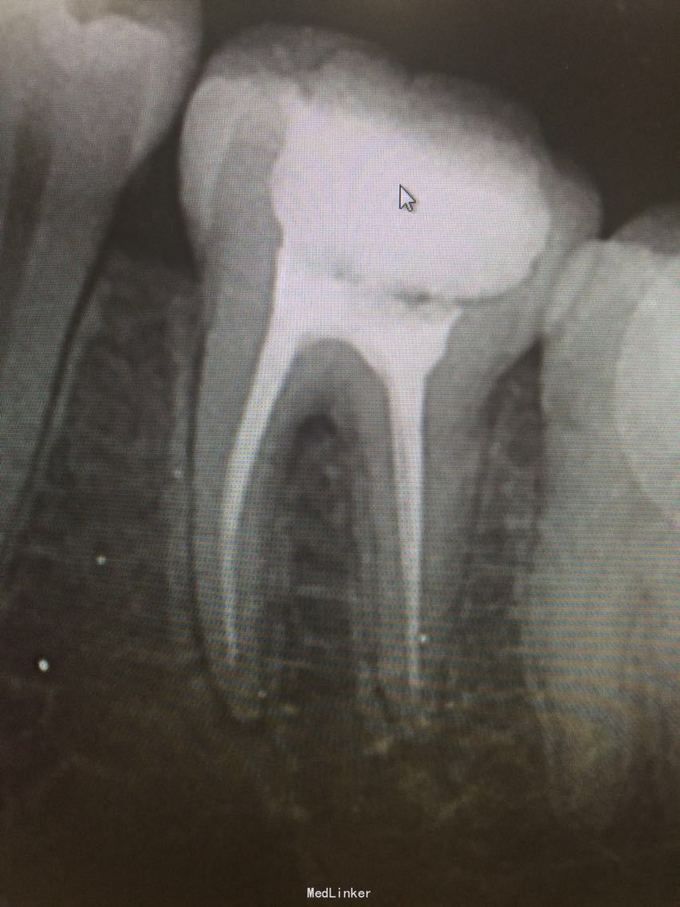

46合面缺损,呈黑褐色洞,探质软,探扣疼痛,

46牙髓炎,处理,根管治疗后树脂堆核,高嵌体修复

无不适,很好用,继续观察,三个月复查